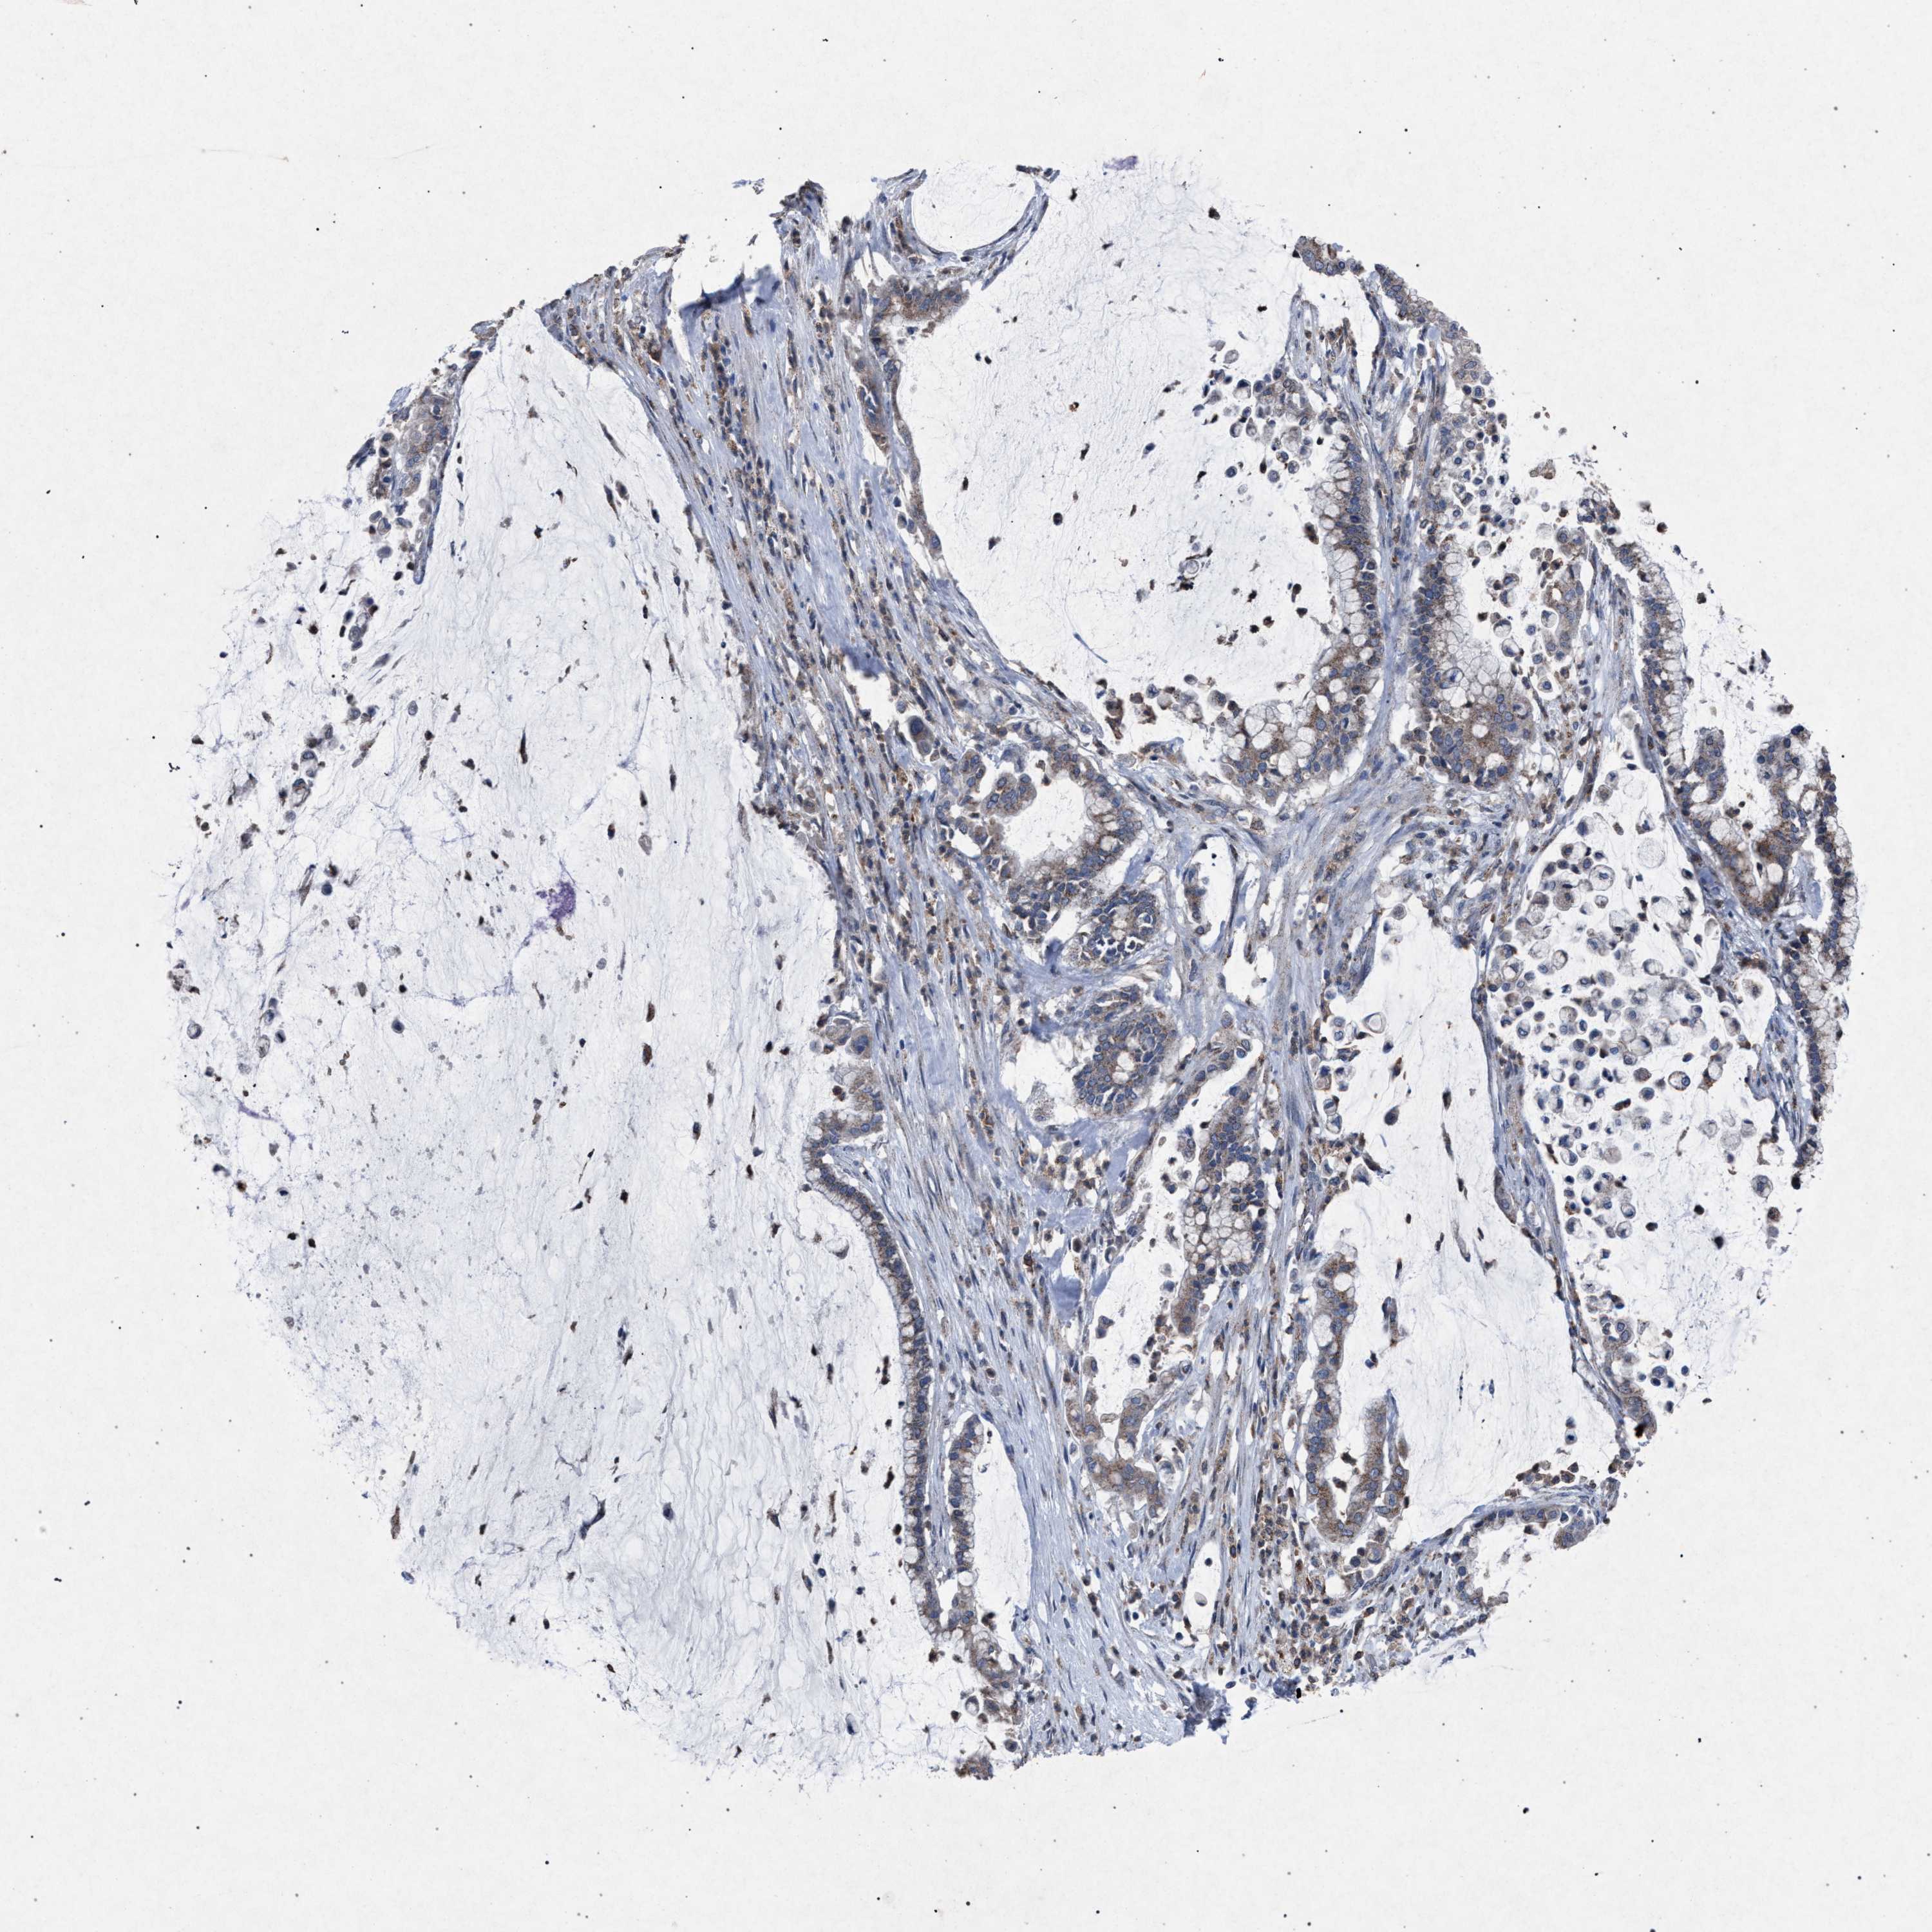

PANCREATIC CANCER - Protein expressioni

A mouse-over function shows sample information and annotation data. Click on an image to view it in a full screen mode. Samples can be filtered based on level of antibody staining by selecting one or several of the following categories: high, medium, low and not detected. The assay and annotation is described here.

Note that samples used for immunohistochemistry by the Human Protein Atlas do not correspond to samples in the TCGA dataset.

Antibody stainingi

Antibody staining in the annotated cell types in the current human tissue is reported as not detected, low, medium, or high, based on conventional immunohistochemistry profiling in selected tissues. This score is based on the combination of the staining intensity and fraction of stained cells.

Each image is clickable and will lead to virtual microscopy that enables deeper exploration of all samples and also displays staining intensity scores, fraction scores and subcellular localization as well as patient and tissue information for each sample.

Antibody HPA021302

Antibody HPA021311

Antibody HPA021479

Adenocarcinoma, NOS